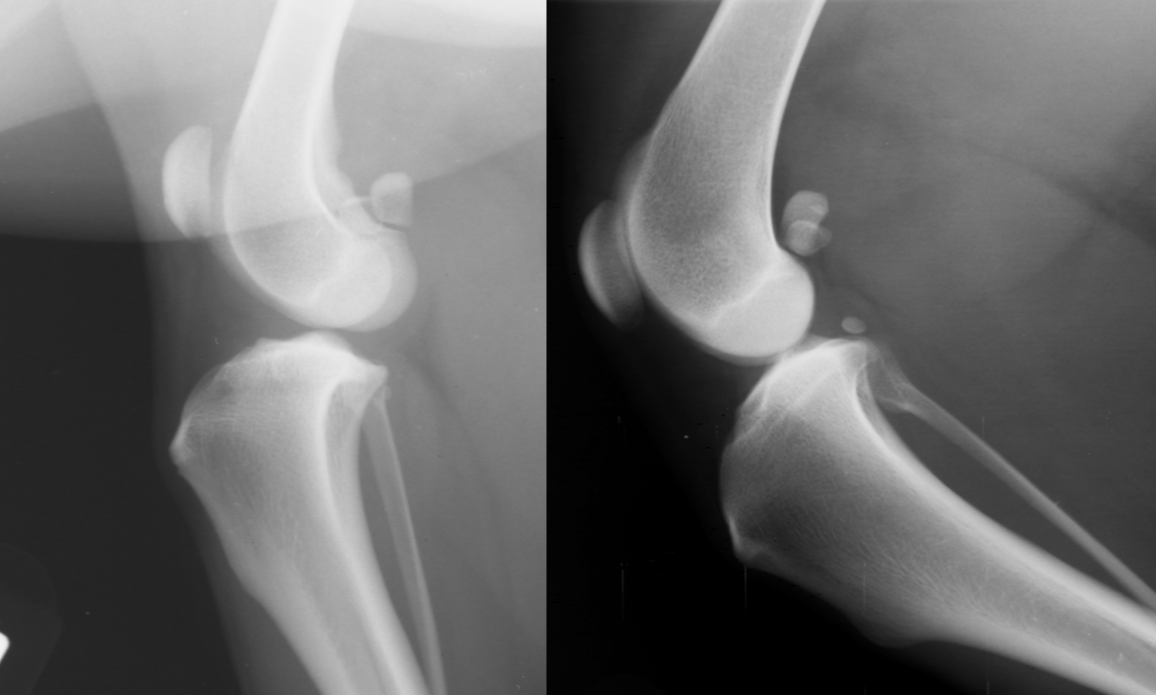

CCL rupture signalment

females

young athletic dogs and middle age overweight dogs

acute, non-wt bearing lameness or insidious onset

tibia displaced cr. , intracapsular swelling

displace fat pad

CCL rupture

septic arthritis signalment

systemic infected/ill or hx of direct injury

AGG lesion

soft tissue swelling

lysis with periosteal rxn

central on joint

multiple joint surfaces

septic arthritis